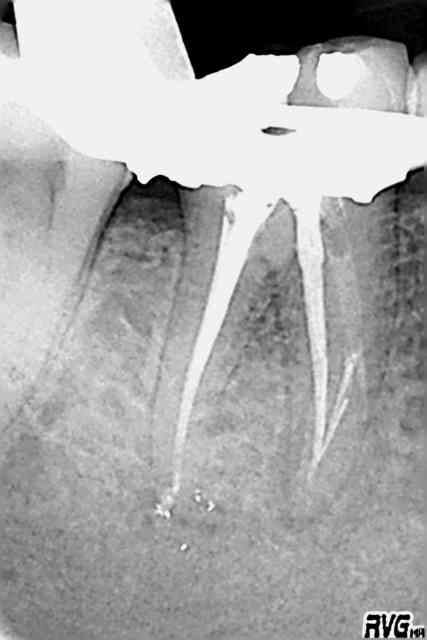

J'ai le même cas, 2 instruments fracturés et un début de fausse route...le tout traité au MTA (bouchon apical sur la fausse route) et gutta chaude dans le reste du canal.

J'ai fait dans la séance, et sous digue, une reconstitution plastique foulée avec un tenon fibré.

La 1è radio pour montrer la nécessité de radios excentrées, la dernière étant le résultat de l'obturation avant la reconstitution composite.